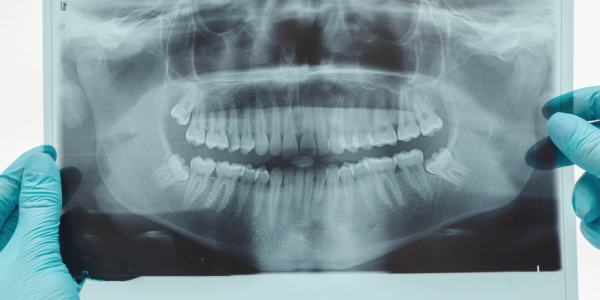

- 눈에 안 보이는 걸 보는 '치과 X-ray 촬영'

마곡동치과_x-ray

초기 치주염은 눈에 안 띄는 게 문제입니다.

그래서 X-ray는 필수입니다.

잇몸뼈가 얼마나 녹았는지, 염증이 어디까지 퍼졌는지를 정확히 보여주니까요.

마치 잇몸 속 지도처럼, 치료 계획을 세우는 데 아주 중요한 역할을 하죠.